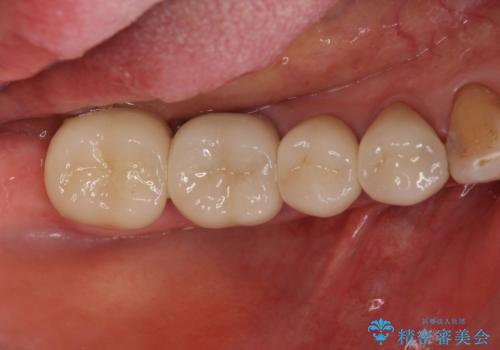

大臼歯 再根管治療

- 27万円(仮歯・ファイバーコア・ジルコニアクラウン・精密根管治療大臼歯再治療)費用は治療当時の料金となります

ただ銀歯を白くするのではなく長期的な予後には歯の内部、根管治療の成功が必要不可欠です。